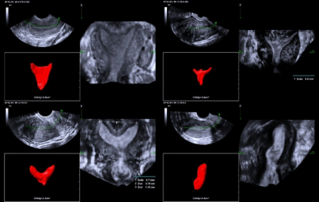

Female pelvic floor anatomy, which developed since the early 20th century, has had a variety of theories, including integral theory, three levels of vaginal support theory, "hammock hypothesis", and three-chamber system. Supporting structures such as pelvic floor muscles, fascia and ligament play an important role in maintaining the normal function of pelvic floor, among which levator ani muscle group is one of the most important supporting structures.